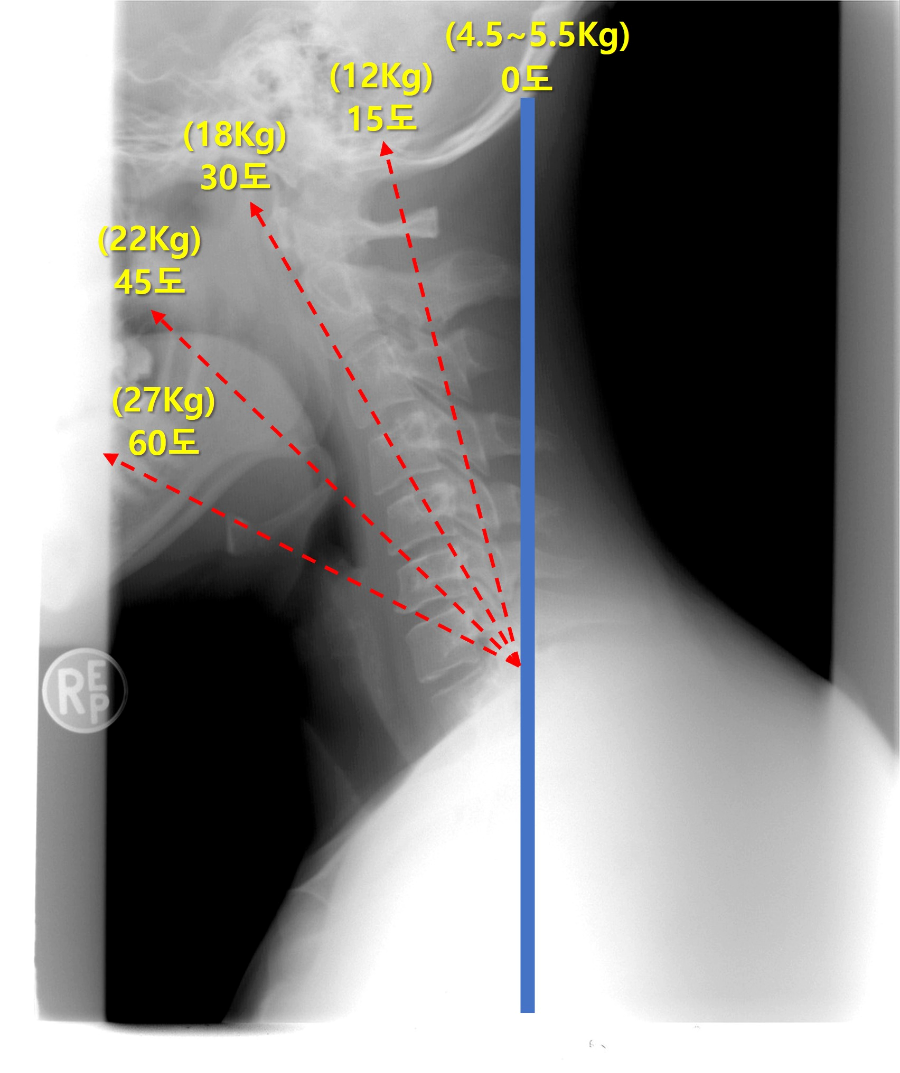

몸을 곧게하게 정면을 보고 서 있을 때의 목뼈의 각도를 0도로 보고, 목을 앞으로 숙여 목뼈의 각도가 5도가 넘어가면 거북목, 11도가 넘어가면 심한 거북목이라고 합니다. 거북목 자세를 오래 하다 보면, 목 근육이 짧아지게 되고 경추의 각도가 C자에서 일자로 바뀌게 됩니다.

목의 경추가 아치형의 C자 곡선을 가져야 목이 머리의 하중을 버틸 수 있는데, 일자로 변형이 되면 지탱할 수 있는 능력이 감소하게 되고 이로 인해 통증이 오게 됩니다.

C자형 목으로 지탱할 머리무게가 4~5Kg 정도 된다고 하면, 일자목으로 변형이 되면 지탱할 무게가 7~8Kg으로 늘어나게 됩니다. 목이 앞으로 구부려지는 거북목 자세가 될수록 목이 지탱해야 하는 무게는 증가됩니다.

사람들이 스마트폰을 볼 때 평균적으로 30도에서 40도 정도 구부린다고 합니다. 목을 앞으로 숙이는 만큼 목은 더 큰 하중을 버텨야 하는데요. 30도를 앞으로 숙이면 머리무게 4~5Kg에 추가로 하중이 가해져 18kg 정도의 무게를 목이 견뎌야 합니다. 60도로 숙이면 무려 27kg의 하중이 걸린다고 합니다.